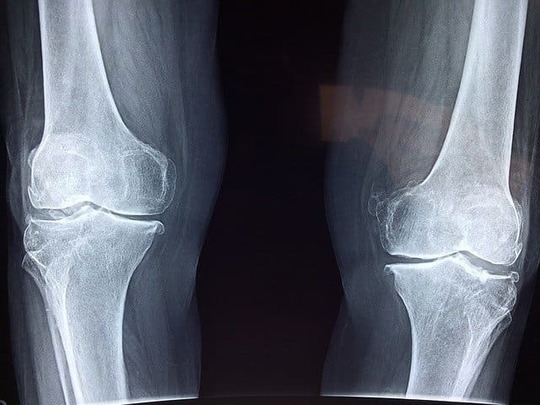

マレットフィンガーの症状は、DIP関節が曲がり、赤くなったり腫れたり圧痛を感じたりすることです。動かした時に痛みを感じることも多いです。

マレットフィンガーの主要な症状で、指先が屈曲し、伸展できなくなります。この症状は、屈筋腱が損傷した際に、指先を伸展するための伸筋腱が反対側に引っ張られることによって引き起こされます。

・指先の変形

指先の屈筋腱が損傷した場合、指先が変形することがあります。例えば、指先が曲がったまま固定されることがあります。

・関節の可動域の制限

マレットフィンガーの場合、指先を伸展するための伸筋腱が損傷するため、指先を伸ばすことができなくなることがあります。これにより、関節の可動域が制限されることがあります。